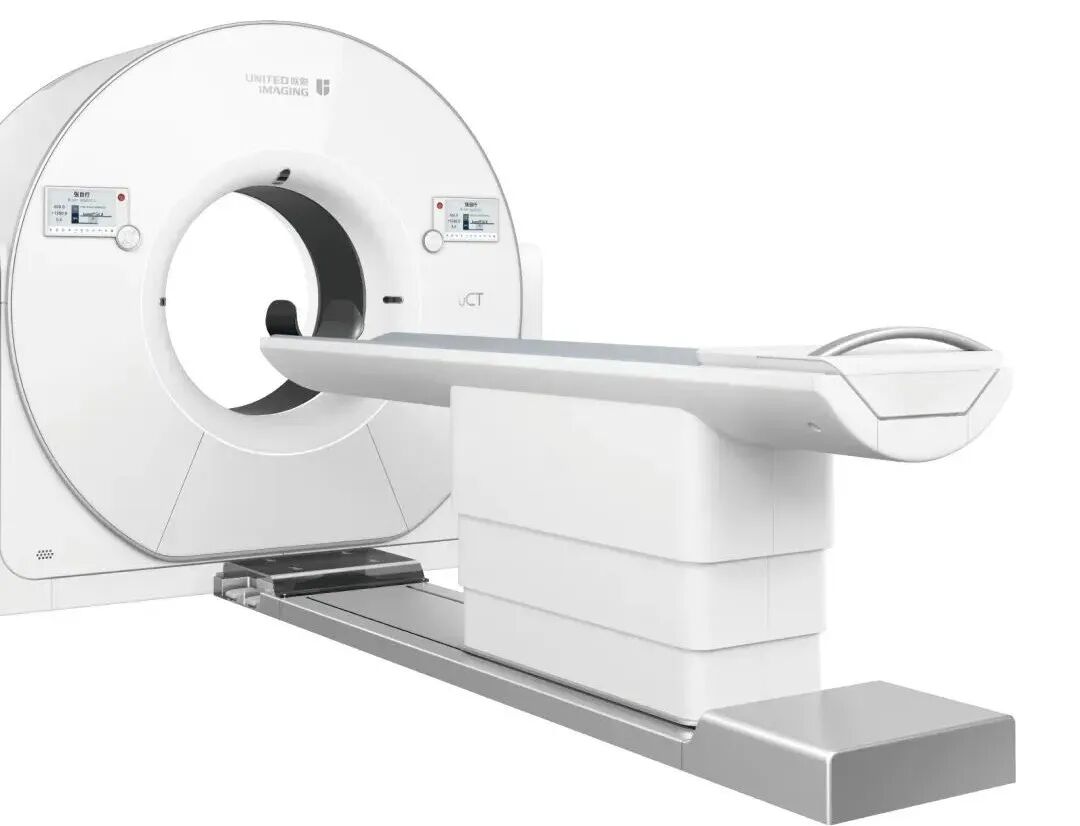

1、荷兰PHILIPS(飞利浦)3.0T高端全数字磁共振 Ingenia;联影640排高端螺旋CT 天河960+;

联影640层CT是中国CT届的“天花板”,集当今CT领域的高精尖科技于一身,将各项临床应用发挥到极致,为患者带来精准、舒适、安全的CT检查新体验。建立了心血管、神经、肿瘤、呼吸系统、泌尿系统及骨科专业等疾病的成像和低剂量筛查领域全新标准,真正实现全方位成像,结合AI人工智能技术,提高疾病诊断率。